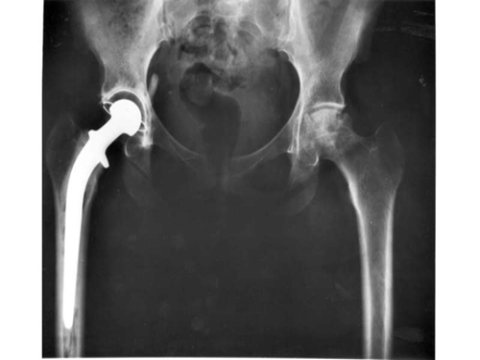

Nghiên cứu cho thấy khớp háng nhân tạo mới có khả năng tồn tại ít nhất 25 năm.